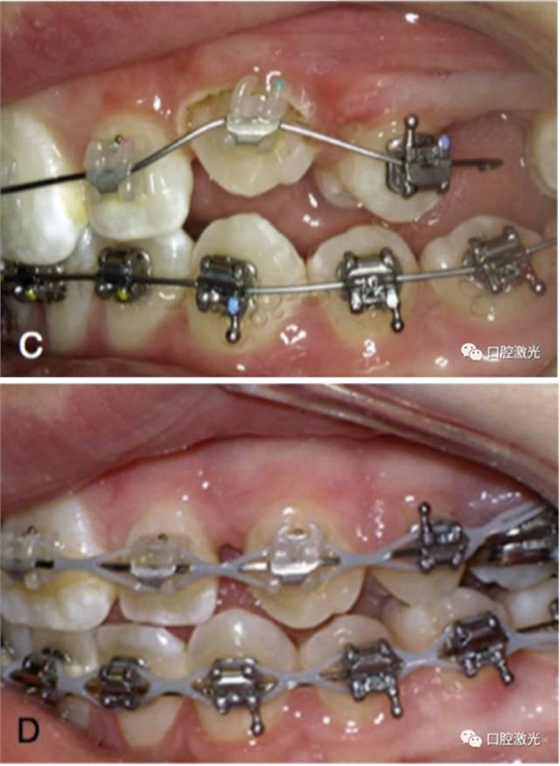

正常情況下,理想的托槽粘接位置為牙冠的中心位置。如果要達到這一目的,正畸牙醫(yī)首先需要能夠從視覺上觀察清楚牙冠的整體形態(tài)。如果存在牙齦覆蓋、遮擋的情況,就很難達到這一目的。這時,簡單的激光牙齦切割就可以很好的增加牙冠的暴露程度,達到更加準(zhǔn)確的粘接托槽的目的,從而也就加快了整個正畸療程的速度。通過下圖的病例可以看到,不僅患者節(jié)約了數(shù)月的等待時間,同時也創(chuàng)造了一個干凈的口腔環(huán)境,降低了在后續(xù)的正畸治療中可能導(dǎo)致牙齦增生的風(fēng)險。

治療前

激光牙齦切割后暴露更多的上前牙便于粘接托槽

當(dāng)天粘接托槽后即刻

4周后即可見明顯效果